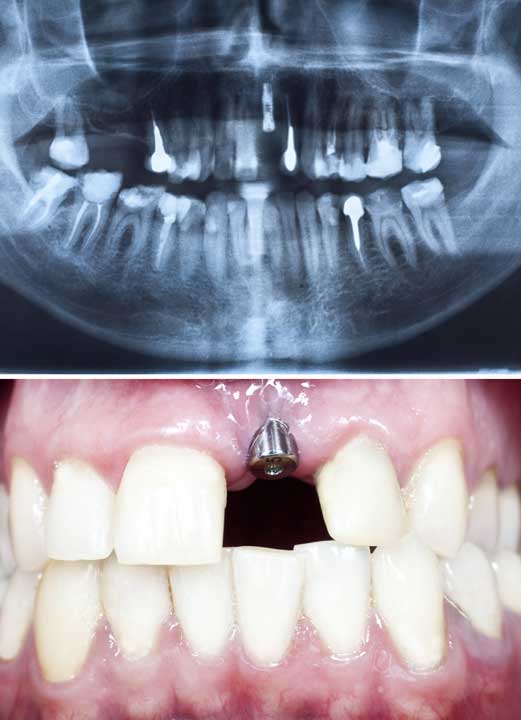

IMPLANTES

¿Qué son los implantes?

Los implantes

dentales osteointegrados son unos dispositivos de titanio, con diferentes tratamientos y recubrimientos de superficie. Su función es la de sustituir las raíces de los dientes naturales, sirviendo de soporte para la conexión, a través de los componentes protésicos, con la restauración definitiva, proporcionando confort, ajuste y estética.

¿Cuándo se colocan?

A cualquier edad

finalizando el crecimiento, siempre y cuando la calidad y cantidad del hueso receptor sea la adecuada. En el caso de que la cantidad de hueso sea insuficiente, se pondrán aplicar técnicas de aporte óseo mediante injertos.